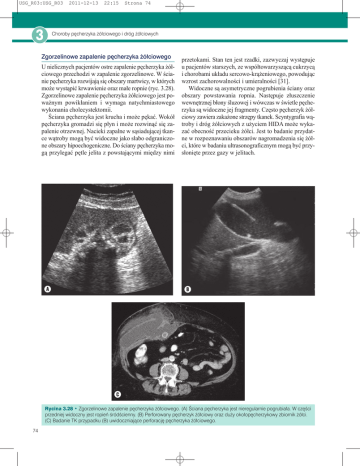

Zgorzelinowe zapalenie pęcherzyka żółciowego

U nielicznych pacjentów ostre zapalenie pęcherzyka żółciowego przechodzi w zapalenie zgorzelinowe. W ścianie pęcherzyka rozwijają się obszary martwicy, w których

może wystąpić krwawienie oraz małe ropnie (ryc. 3.28).

Zgorzelinowe zapalenie pęcherzyka żółciowego jest poważnym powikłaniem i wymaga natychmiastowego

wykonania cholecystektomii.

Ściana pęcherzyka jest krucha i może pękać. Wokół

pęcherzyka gromadzi się płyn i może rozwinąć się zapalenie otrzewnej. Nacieki zapalne w sąsiadującej tkance wątroby mogą być widoczne jako słabo odgraniczone obszary hipoechogeniczne. Do ściany pęcherzyka mogą przylegać pętle jelita z powstającymi między nimi

przetokami. Stan ten jest rzadki, zazwyczaj występuje

u pacjentów starszych, ze współtowarzyszącą cukrzycą

i chorobami układu sercowo-krążeniowego, powodując

wzrost zachorowalności i umieralności [31].

Widoczne są asymetryczne pogrubienia ściany oraz

obszary powstawania ropnia. Następuje złuszczenie

wewnętrznej błony śluzowej i wówczas w świetle pęcherzyka są widoczne jej fragmenty. Często pęcherzyk żółciowy zawiera zakażone strzępy tkanek. Scyntygrafia wątroby i dróg żółciowych z użyciem HIDA może wykazać obecność przecieku żółci. Jest to badanie przydatne w rozpoznawaniu obszarów nagromadzenia się żółci, które w badaniu ultrasonograficznym mogą być przysłonięte przez gazy w jelitach.

Rycina 3.28 • Zgorzelinowe zapalenie pęcherzyka żółciowego. (A) Ściana pęcherzyka jest nieregularnie pogrubiała. W części

przedniej widoczny jest ropień śródścienny. (B) Perforowany pęcherzyk żółciowy oraz duży okołopęcherzykowy zbiornik żółci.